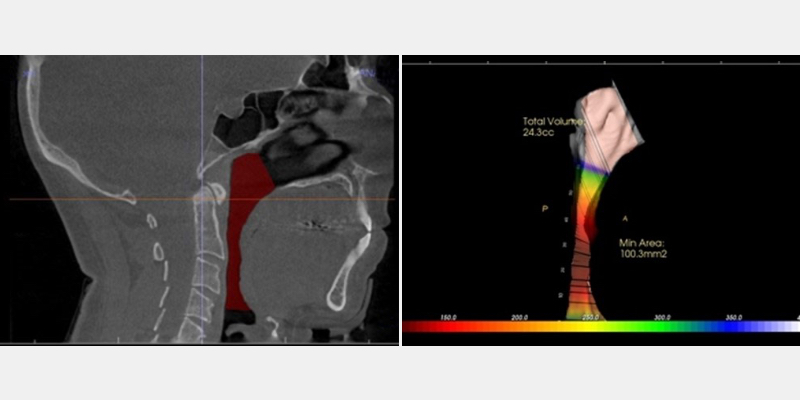

Airway Volume

Images of the airway space and the overall airway volume are beneficial when trying to understand the impact of the soft tissue and its effect on airflow. While Figure 4 is a “snapshot” of a patient’s anatomy, it can provide insight into the cause and effect and the potential chokepoint, which is the area where the tissue can close off, impairing breathing.

Typically, a normal range is 150.0 mm, so if a patient, for example, shows a volume of 50.0 mm, a practitioner would want to consider ordering a sleep screening test to rule out an SRD.